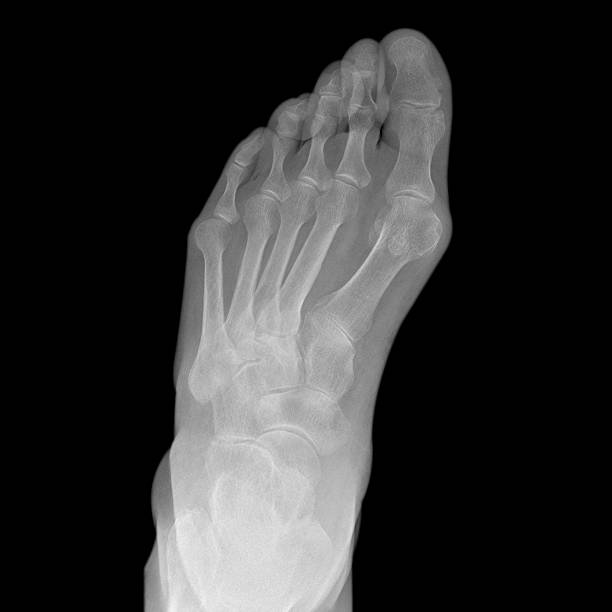

발은 제2의 심장이라고 부를 만큼 우리 몸의 중요한 역할을 하는 신체기관이며 동시에 우리 몸의 체중을 모두 지지하는 구조이기 때문에 관리가 중요하지만 현실적으로 건강관리에 있어서 맨 첫줄에 서기는 어려운 신체기관입니다. 따라서 관리의 영역보다는 이미 어느 정도 통증이 생기고 나서야 병원을 방문하게 되어 치료에 어려움을 겪게 되는데 실제는 질환 종류도 각각 다양하기 때문에 정확히 아는 것이 중요합니다.

발뒤꿈치가 아픈 이유 첫 번째는 족저근막염입니다. 족저근막은 발뒤꿈치 뼈에서 시작하여 발바닥 앞쪽으로 연결되는 두껍고 강한 섬유질 띠입니다. 족저근막은 우리 몸의 중요한 역할을 하는데 아치 모양의 모양새는 우리 몸의 체중을 흡수하기 때문에 걷는 데 중요한 역할을 할 수 있습니다. 족저근막염은 이러한 족저근막에 반복되는 충격으로 근막을 둘러싸고 있는 콜라겐이 변성하면서 염증이 생긴 것을 의미합니다.

이러한 증상은 원래부터 평발이거나 걸음걸이나 생활습관 등으로 발이 변형되며 구조적으로 이상이 생겨서 문제가 생길 수도 있지만 기본적으로 하체 사용을 무리하게 하다보면 문제가 생기게 됩니다. 족저근막염 통증은 개인에 따라 다르지만 기본적으로 발뒤꿈치에 통증을 느끼게 되고 특히 아침 기상후 첫 걸음부터 통증이 나기 때문에 조기에 치료를 받는 것이 중요합니다.